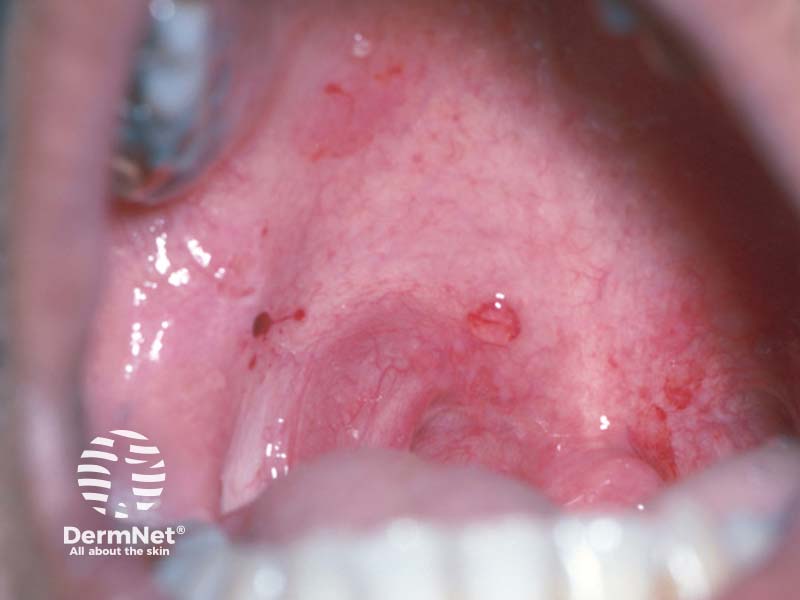

Placeholder image

Oral ulcers and new skin blisters

Read moreArrow right small right